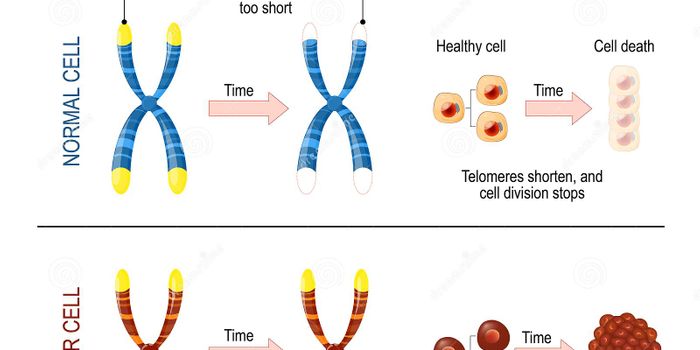

OCT 05, 2021Genetics & GenomicsAs our body ages, cells have to divide to replenish those that become worn out or damaged. Most cells also carry the gen ...

AUG 01, 2021Genetics & GenomicsThroughout our lives, new cells often replace the ones that become damaged or worn out. As cells divide, they have to re ...

DEC 24, 2020Genetics & GenomicsMany types of cells have to be replenished throughout our lives, and cells divide to replace those that are damaged or w ...

NOV 15, 2020Genetics & GenomicsCells have to be able to divide so new ones can replenish cells that get worn out, dysfunctional, or that accumulate dam ...

SEP 11, 2020Genetics & GenomicsTelomeres cap the ends of chromosomes. They work to protect the chromosomes from degradation, and are known to get short ...